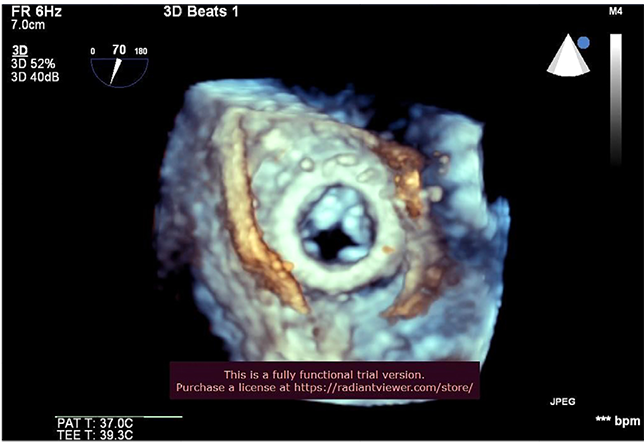

Представлен первый опыт имплантации отечественного транскатетерного протеза «МедЛаб-КТ» в трикуспидальную позицию. Процедуру проводили пациенту высокого хирургического риска с пятью «открытыми» оперативными вмешательствами по поводу аномалии Эбштейна в анамнезе, у которого развилась дисфункция ранее установленного биологического протеза. Имплантацию осуществляли трансатриальным доступом «клапан-в-клапан» в позицию биологического протеза. Послеоперационный период протекал без осложнений. Отечественный транскатетерный политетрафторэтиленовый протез «МедЛаб-КТ» эффективен и безопасен при имплантации «клапан-в-клапан» в случае дисфункции биологического протеза в трикуспидальной позиции.